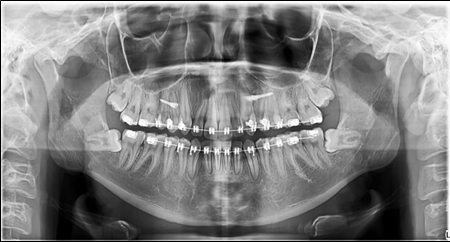

Before the finishing stage, a panoramic x-ray was taken. The third molars were removed .(Figure 6)

Figure 6.Panoramic X-ray before the removal of the third molars.

Panoramic X-ray before the removal of the third molars.